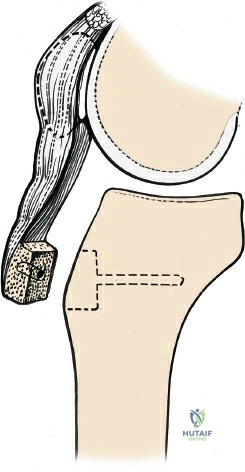

- Correction of Patellofemoral Malalignment:

- Procedures such as tibial tubercle osteotomy (e.g., Elmslie-Trillat, Fulkerson) for patellar instability or anterior knee pain, often performed via a modified medial parapatellar skin incision.

- Extensive Patella Baja: In cases of severe patella baja (inferior patellar position), exposure of the trochlea and proximal tibia can be significantly limited, potentially necessitating an extensile approach like a V-Y quadriceps plasty or tibial tubercle osteotomy.

1. Skin Incision

The incision typically begins approximately 3-5 cm proximal to the superior pole of the patella, curves slightly medially along the patellar border, and extends distally parallel to the medial border of the patellar tendon, terminating approximately 2-3 cm distal to the tibial tubercle. A straight midline longitudinal incision is an alternative, particularly when combined with a medial parapatellar capsular approach for TKA, offering a large exposure. The length and curvature of the incision are tailored to the specific procedure and patient anatomy.

- Total Knee Arthroplasty (TKA): Once exposed, the distal femoral and proximal tibial bone cuts are performed, often guided by intramedullary or extramedullary alignment systems. Ligament balancing is then achieved through sequential releases.

Initial bone cuts in Total Knee Arthroplasty, demonstrating the precise surgical field achieved with the medial parapatellar approach.

Further bone resections in TKA, highlighting the unobstructed view for accurate jig placement and cutting. - Fracture Fixation: Reduction of fracture fragments under direct visualization, followed by temporary fixation with K-wires, then definitive fixation with plates, screws, or cerclage wires as dictated by the fracture pattern.